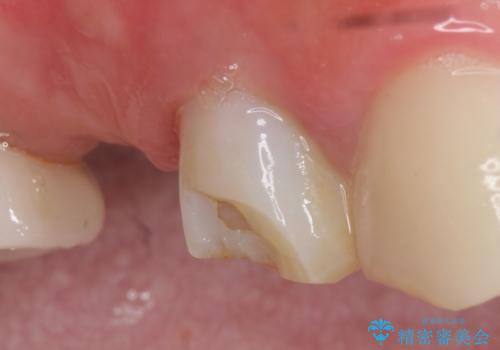

- アメリカの歯科医院にて治療途中の歯の仮歯が割れてしまったので診て欲しいといらっしゃった方の症例です。

しばらくアメリカに戻れそうにないため、当院での治療を希望。土台の築造まで処置は終わっているとのことだったのでオールセラミッククラウンによる補綴のみを行いました。

※遠心の欠損部はアメリカにてインプラント予定とのこと。